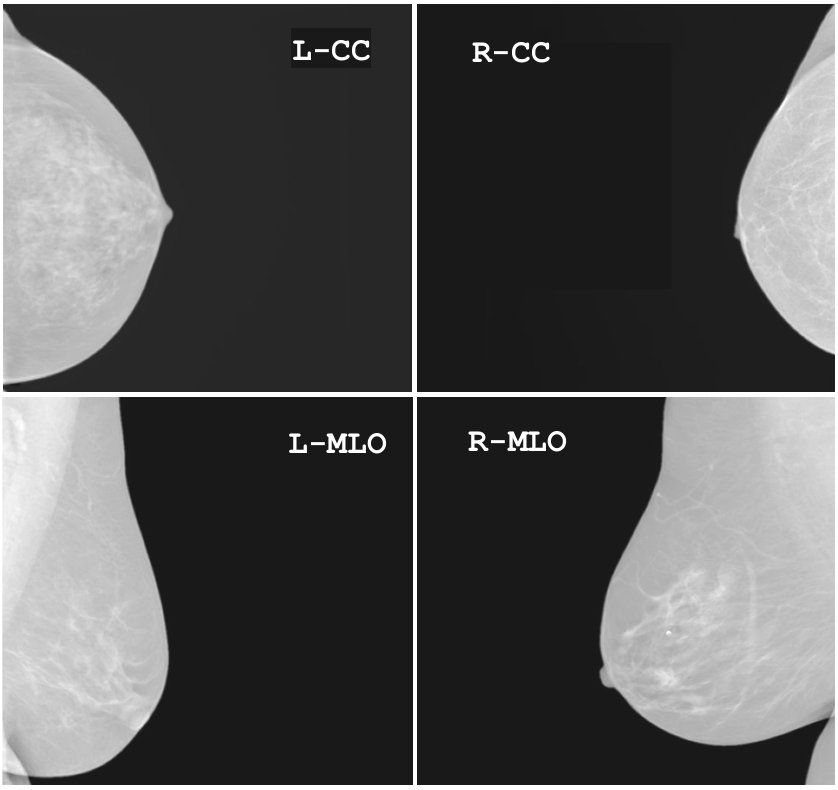

4-Views